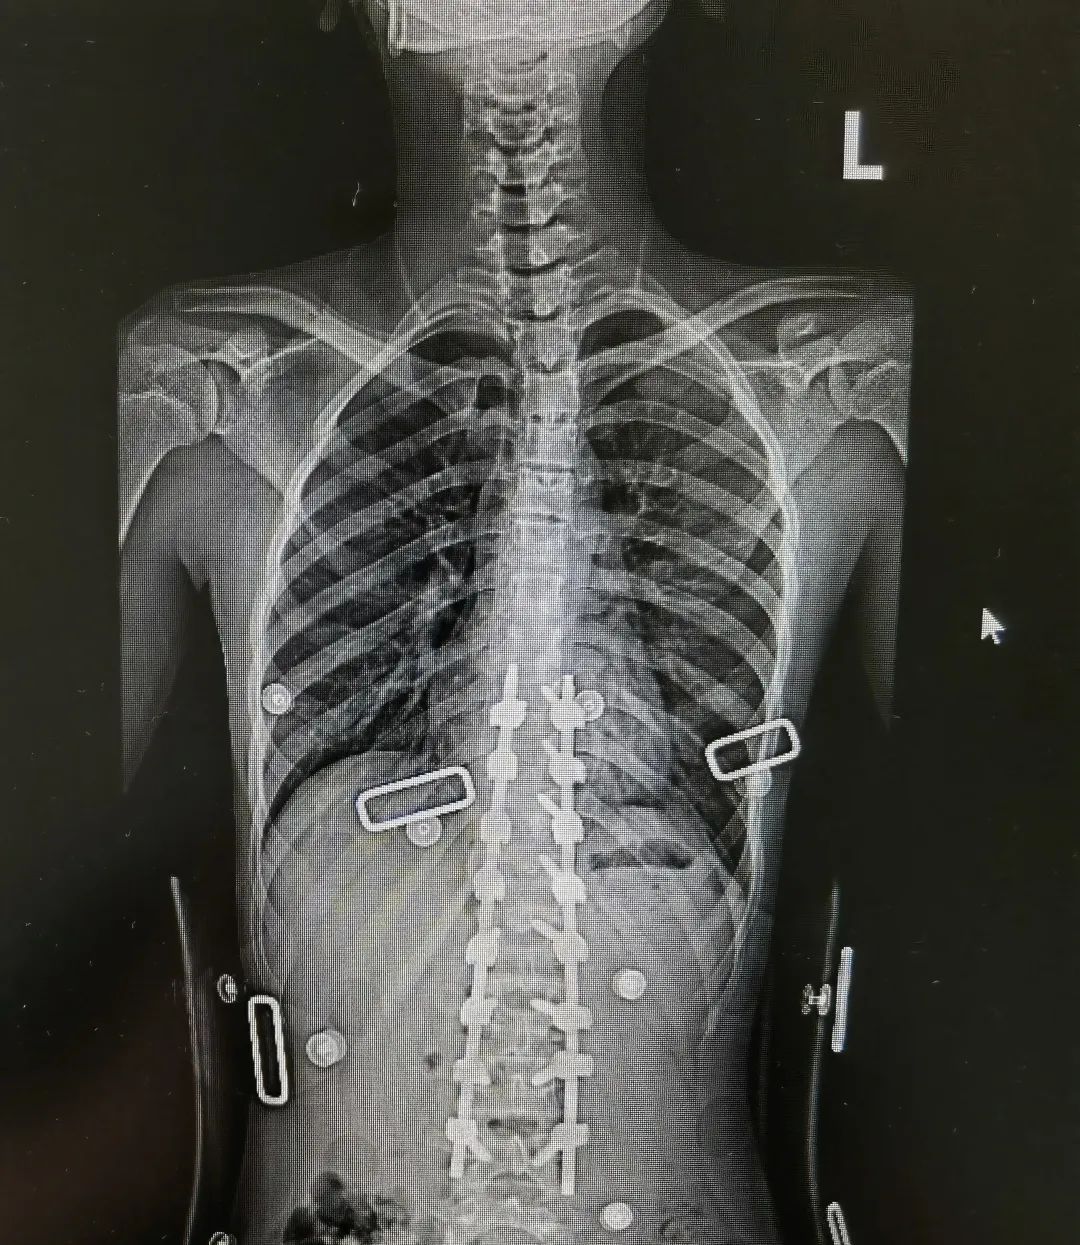

先天性脊柱侧弯半椎体畸形术前术后图

陈文昊副主任介绍,每个人的脊椎由两个成骨中心,两边合在一起,逐渐成为一个椎体。如果只有一侧成骨,则形成半个椎体。半椎体引起的脊柱侧弯和孩子平时的坐姿不良没有关系,它是由于脊柱在胚胎时期出现脊椎的分节不完全、一侧有骨桥或者一侧椎体发育不完全或者混合有上述两种因素,造成脊柱两侧生长不对称,从而引起脊柱侧弯。

“家长需要注意的是,如果孩子还没到青春期,就发现有脊柱侧弯的倾向,就要考虑是否可能是先天因素引起,建议带孩子到医院进行排查,而不是简单归为坐姿问题,不然可能会延误治疗。”陈文昊说。